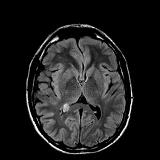

Rationale: Epilepsy is a cause of major morbidity in Sturge Weber syndrome, a segmental vascular neurocutaneous disorder classically associated with facial angiomas, glaucoma, and leptomeningeal capillary-venous type vascular malformations. Seizures occur in more than 75% of affected individuals and are a challenge to treat. The phenomenon of prolonged ictal paresis is a rare seizure sign that can be due to lesions affecting the centro-parietal lobe. Use of steroids to treat leptomeningeal inflammation resulting from angiomatosis of Sturge Weber syndrome has not been reported. Methods: Case Report : A case of a patient with Sturge Weber syndrome presenting with partial seizure like episodes with prolonged post-ictal paralysis, extensive leptomeningeal T2 hyperintensity noted on MRI with good response to Dexamethasone Results: A 24 year male was brought to our hospital after developing persistent left hemiparesis. He had been having brief spells of right sided headache and left hemiparesis for the past 18 months and was on Oxcabazepine for presumed seizure with post-ictal paralysis. He reported recent subtle twitching of the left face and eyes, left hemiparesis and psychomotor slowing with right frontal-temporal headaches but deficits were not resolving like prior episodes. His initial examination showed dysarthria, left homonymous hemianopia, left sided facial weakness, left hemiparesis and left hemianesthesia and although no clinical seizures were noted at this time, Valproic Acid was added for suspected partial status epilepticus and post-ictal paralysis. A 24 hour cEEG showed diffuse right hemispheric slowing, but no ictal activity. MRI brain with contrast showed extensive leptomeningeal FLAIR hyperintensity and enhancement throughout the right cerebral hemisphere consistent with leptomeningeal angiomatosis as well as prominent venous flow voids. Cerebral angiogram showed absence of right hemispheric cortical veins and aberrant venous outflow through multiple pathways, but no AVM or dural AV fistula. After 9 days of persistent deficits, he was started on Dexamethasone 4 mg every 6 hours, which was tapered to 2 mg Q6H with significant improvement in his headaches, left arm strength and communication skills within the next 3 days, and he was discharged with a tapering regimen over 10 days. MRI brain 5 weeks later showed interval decrease in size of previously noted dilated flow voids within the right parietal lobe and collateral draining veins. There was near complete resolution of previously noted leptomeningeal FLAIR hyperintensity. Follow up neurological examination 6 weeks post-discharge showed complete resolution of his neurologic deficits and spells. Conclusions: We report a case of persistent left hemiparesis in a patient with Sturge Weber syndrome attributed to leptomeningeal inflammation of the right cortical hemisphere which showed interval improvement of radiological findings and resolution of neurological deficits with Dexamethasone treatment. Conclusions: We report a case of persistent left hemiparesis in a patient with Sturge Weber syndrome attributed to leptomeningeal inflammation of the right cortical hemisphere which showed interval improvement of radiological findings and resolution of neurological deficits with Dexamethasone treatment. Funding: No funding was received in support of this abstract.